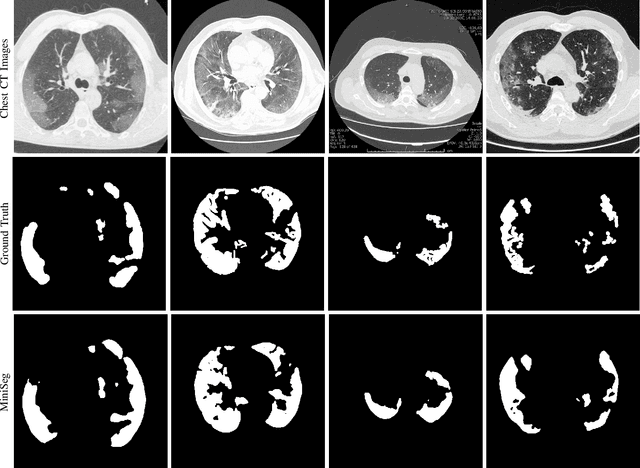

Abstract:The rapid spread of the new pandemic, coronavirus disease 2019 (COVID-19), has seriously threatened global health. The gold standard for COVID-19 diagnosis is the tried-and-true polymerase chain reaction (PCR), but PCR is a laborious, time-consuming and complicated manual process that is in short supply. Deep learning based computer-aided screening, e.g., infection segmentation, is thus viewed as an alternative due to its great successes in medical imaging. However, the publicly available COVID-19 training data are limited, which would easily cause overfitting of traditional deep learning methods that are usually data-hungry with millions of parameters. On the other hand, fast training/testing and low computational cost are also important for quick deployment and development of computer-aided COVID-19 screening systems, but traditional deep learning methods, especially for image segmentation, are usually computationally intensive. To address the above problems, we propose MiniSeg, a lightweight deep learning model for efficient COVID-19 segmentation. Compared with traditional segmentation methods, MiniSeg has several significant strengths: i) it only has 472K parameters and is thus not easy to overfit; ii) it has high computational efficiency and is thus convenient for practical deployment; iii) it can be fast retrained by other users using their private COVID-19 data for further improving performance. In addition, we build a comprehensive COVID-19 segmentation benchmark for comparing MiniSeg with traditional methods. Code and models will be released to promote the research and practical deployment for computer-aided COVID-19 screening.